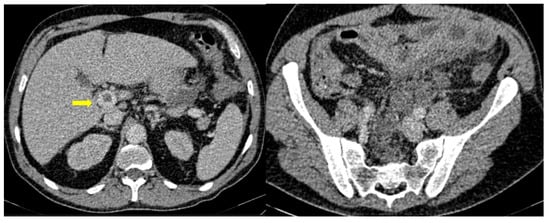

Figure 1. COVID-19 (+) hospitalized 75-year-old male patient with abdominal pain and diarrhea. Abdominal Contrast Enhanced CT (CECT) depicted bowel wall thickening ((a), thick arrow) and mesenteric fat stranding ((b), thin arrow). The imaging findings are indicative of inflammatory colitis.

A large bowel infection usually appears with diffuse circumferential and enhancing wall thickening (hyperenhancement) that can involve one or more segments of the colon (Figure 1 and Figure 2). Pericolic fluid or perintestinal fat stranding is common while pericolic lymphadenopathy is not (Figure 3 and Figure 4). If we suspect COVID-19-related colitis, clinical correlation is needed, and the detection of the virus in stools can establish the diagnosis.